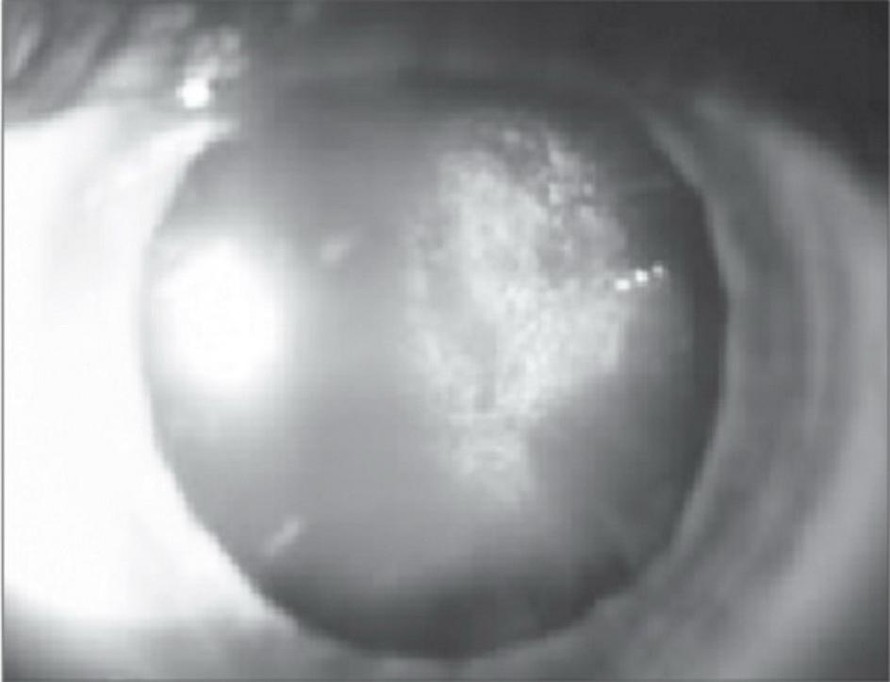

Đục thể thủy tinh dưới vỏ sau do steroid.

Nhóm thuốc này gây đục thể thủy tinh khá đặc trưng, là đục thể thủy tinh dưới vỏ sau vùng trung tâm. Cơ chế gây bệnh còn nhiều tranh cãi nhưng nhiều tác giả cho là do ảnh hưởng đến cân bằng cytokine và các chất tăng trưởng nội nhãn.